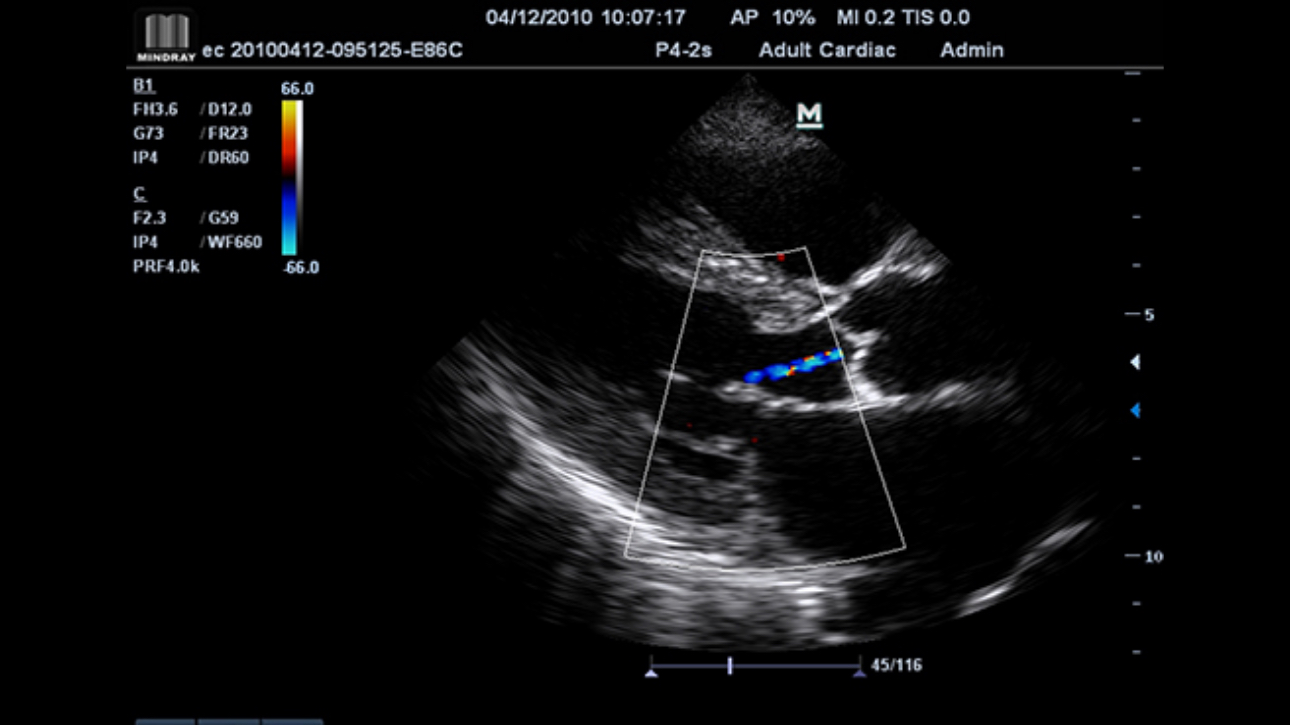

Award winning portable hand-carried color Doppler, M7 Premium is a High level system with excellent performance. Equipped with dedicated cardiac package and easy-to-use workflow software, M7 Premium offers an ideal packaged solution to address the needs of cardiologists.

Performance

PSHITM (Phase Shift Harmonic Imaging)

Purified Harmonic Imaging for better contrast resolution providing clearer images with excellent resolution and less noise.

iBeamTM(Spatial Compound Imaging)

Permits use of multiple scanned angles to form a single image, resulting in enhanced contrast resolution and improved visualization.